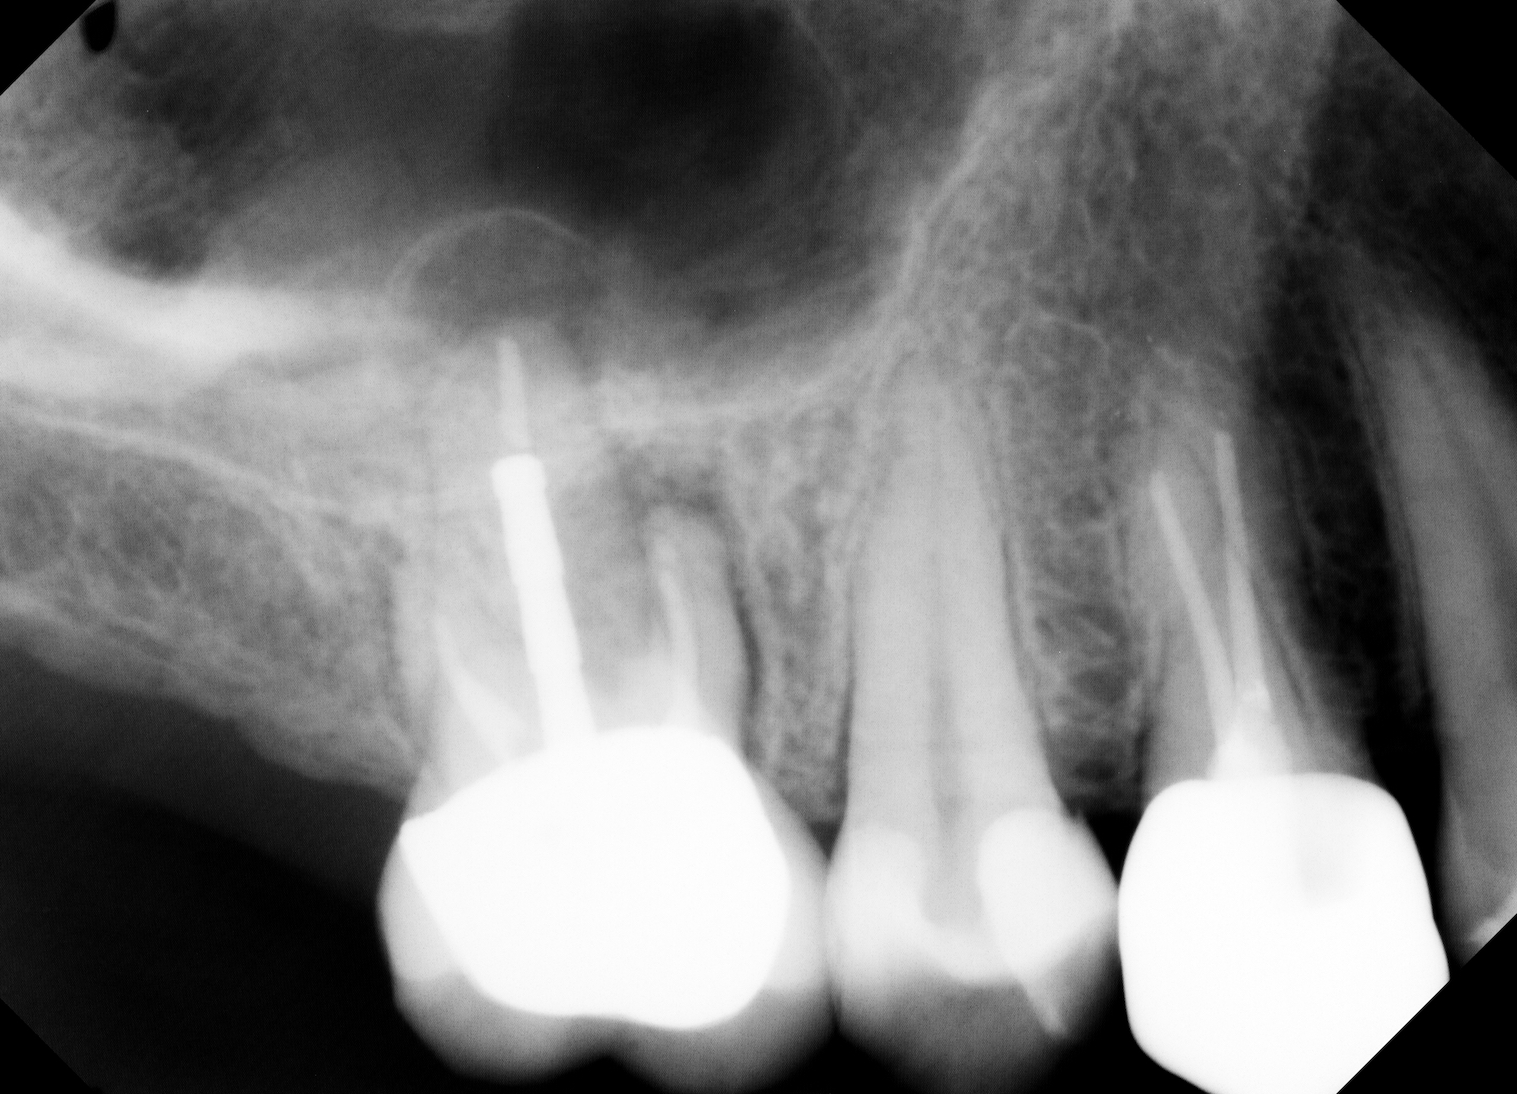

As direct implant costs have gone down, the simplification and efficiency of many implant procedures have contributed to what many are calling the “golden age of implant dentistry.” The advent of short implants—and research articles backing the success rate of short implants—has reduced the need for more extensive grafting procedures. This is one clinical area that has allowed more general practitioners to place more implants due to the simplified sinus-area procedures. In areas of 6 mm or more of maxillary bone height, clinicians are able to provide a minimally invasive sinus bump and achieve bicortical stabilization. Implants such as the iHex and MorsTorq were designed with a rounded end to safely provide this procedure. The taper of these and similar systems also protects the implant from being lodged apically into the sinus cavity, thus making it user-friendly for beginner to intermediate implantologists.

Therefore, if a patient has 5 mm of available bone height from the sinus floor, a maximum of 5 mm is prudent to expect from an indirect lift; therefore, an 8 mm to 10 mm implant is the ideal choice. The tapered iHex or MorsTorq implant provides safety when dealing with sinus areas, for three reasons. First, the taper helps prevent overinsertion toward the sinus cavity. Second, the abutment and transfer attached to the implant allows for more control. Finally, the rounded apex helps reflect the sinus floor without creating damage (figures 1-6).